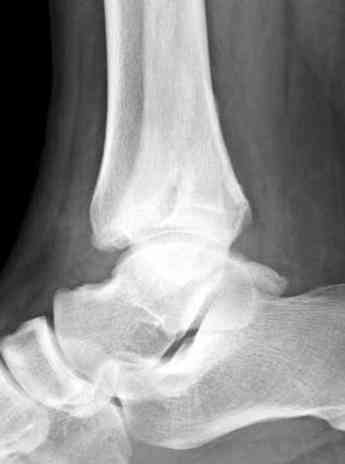

Мне кажется есть все основания попытаться сделать остеосинтез. Боль вследствие нестабильности. Нестабильность вследствие неанатомичного положения дистального отломка малоберцовой кости. Через 1,5 вполне возможно разобщить, репонировать и фиксировать длинный косой перелом наружной лодыжки. Вероятно, одновременно придется делать медиальный доступ для мобилизации внутренней лодыжки. Мы оперируем таких пациентов, функциональные (объем движений) результаты конечно хуже по сравнению с теми кого оперируем в первые 5-10 дней, но вполне удовлетворительные.

Согласен, на предоставленных рентгенограммах все основания для проведения открытого остеосинтеза.

сроки действительно небольшие, но если мы его и возьмем, то пройдет еще минимум неделя, кроме того смущает впечатление сращения н/лодыжки, похоже, что придется не разобщать,а остеотомировать, формирование оссификатов в полости сустава с медиальной стороны, да и сам пациент 1,5 месяца по поводу своей травмы сильно не напрягался

Здесь представлено решение похожей проблемы. Больной в течение года лечился консервативными мерами, и боли в голеностопе были основным показанием к операции.

Проведена обычная стандартная процедура по исправлению неудовлетворительного состояния голеностопного сустава, где кроме удлинения малоберцовой с применением compression tension device за проксимальный конец пластины, проведено замещение трикортикальным графтом из крыла, освобождение синдесмоза и медиальной щели от

фибротических масс с фиксацией.